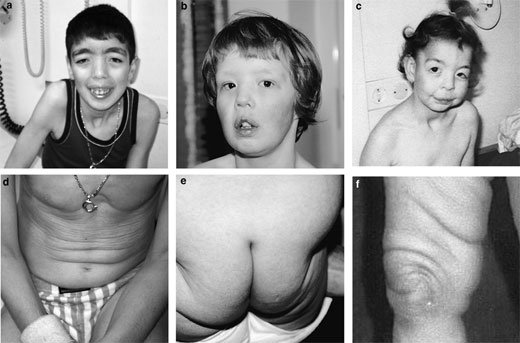

La Cutis Laxa (CL)

La cutis laxa (CL) es una afectación hereditaria o adquirida del tejido conectivo. Se caracteriza por una piel arrugada, abundante y flácida, que ha perdido su elasticidad, y se asocia con anomalías esqueléticas o del desarrollo y, en algunos casos, con una afectación sistémica grave. No existe un tratamiento eficaz para la CL y el manejo es sintomático.

Se caracteriza por una piel arrugada, abundante y flácida, que ha perdido su elasticidad, y se asocia con anomalías esqueléticas o del desarrollo y, en algunos casos, con una afectación sistémica grave.

La mayoría de los casos de CL son hereditarios. Su prevalencia al nacimiento se estima en 1/1.000.000 y hasta el momento, sólo se han descrito unas 200 familias en la literatura.

Se han descrito numerosas variantes de CL, que se diferencian según el modo de transmisión hereditario, la extensión de la afectación visceral, las anomalías asociadas y la gravedad de la enfermedad.

Las formas autosómicas recesivas de CL (ARCL) parecen ser las más frecuentes, habiendose descrito dos subtipos: ARCL1 y ARCL2.

La ARCL1 es la forma más grave, con una afectación generalizada que puede ocasionar complicaciones que condicionan el pronóstico vital (enfisema pulmonar y atelectesias, anomalías vasculares, y devertículos en el tracto gastrointestinal y genitourinario).

La ARCL2 incluye un espectro de enfermedades de gravedad variable, desde el síndrome de la piel arrugada, hasta procesos más graves asociados a retraso del crecimiento, anomalías del desarrollo y esqueléticas (ARCL2 clásica, tipo Debré).

El síndrome de De Barsy y la gerodermia osteodisplástica pueden presentan un importante solapamiento clínico con la ARCL2.

El síndrome del cuerno occipital (cutis laxa ligada al X (XRCL) es muy parecido a la ARCL2; aunque algunos pacientes presentan un fenotipo más grave y afectación sistémica.

La CL autosómica dominante (ADCL) suele manifestarse por una afectación leve, aunque se han descrito algunos casos con manifestaciones sistémicas (hernias, anomalías valvulares cardíacas, manifestaciones cardiovasculares, divertículos gastrointestinales y enfisema).

Aunque desconocemos los mecanismos etiológicos subyacentes, en muchos pacientes con las formas hereditarias de CL, se han implicado varios genes: FBLN5 , EFEMP2 y LTBP4 en la ARCL1 (14q32.1, 11q13 y 19q13.1-q13.2), ATP6V0A2 y PYCR1 en la ARCL2 (12q24.3 y 17q25.3), y ELN y FBLN5 en la ADCL (7q11.2 y 14q32.1)).

En pacientes con una forma leve de ARCL, se han identificado también mutaciones homocigotas del gen ELN.

El diagnóstico suele ser difícil como consecuencia del solapamiento clínico entre las formas hereditarias.

La aproximación diagnóstica debe incluir: un examen físico detallado, historial familiar, examen esquelético, evaluación del desarrollo, estudios de imagen, estudio histopatológico, bioquímica convencional y pruebas de función hepática, ecografía renal y valoración oftalmológica y cardíaca.

El principal diagnóstico diferencial debe establecerse con los síndromes de Ehlers-Danlos y con diversas entidades que pueden presentar manifestaciones cutáneas similares, como: síndrome de Williams, pseudoxantoma elástico, síndrome de Hutchinson Gilford, síndrome de Barber Say, síndrome de Costello, síndrome cardio-facio-cutáneo y síndrome de Kabuki.

Las formas hereditarias de CL deben distinguirse asimismo de la CL adquirida, que normalmente suele presentar previo al descarrollo de la CL lesiones inflamatorias localizadas o generalizadas, urticaria, angioedema o reacciones de hipersensibilidad.

Para ofrecer un consejo genético, resulta fundamental establecer un diagnóstico correcto en las formas hereditarias.

Puede practicarse un diagnóstico prenatal por análisis molecular en las familias en las que se ha identificado una anomalía genética.

No existe un tratamiento eficaz para la CL y el manejo es sintomático.

La cirugía plástica por lo general no está indicada para las manifestaciones cutáneas de las formas hereditarias.

El pronóstico es variable: desde una evolución fatal en los niños afectados de ARCL1 hasta una esperanza de vida normal en las formas menos graves.